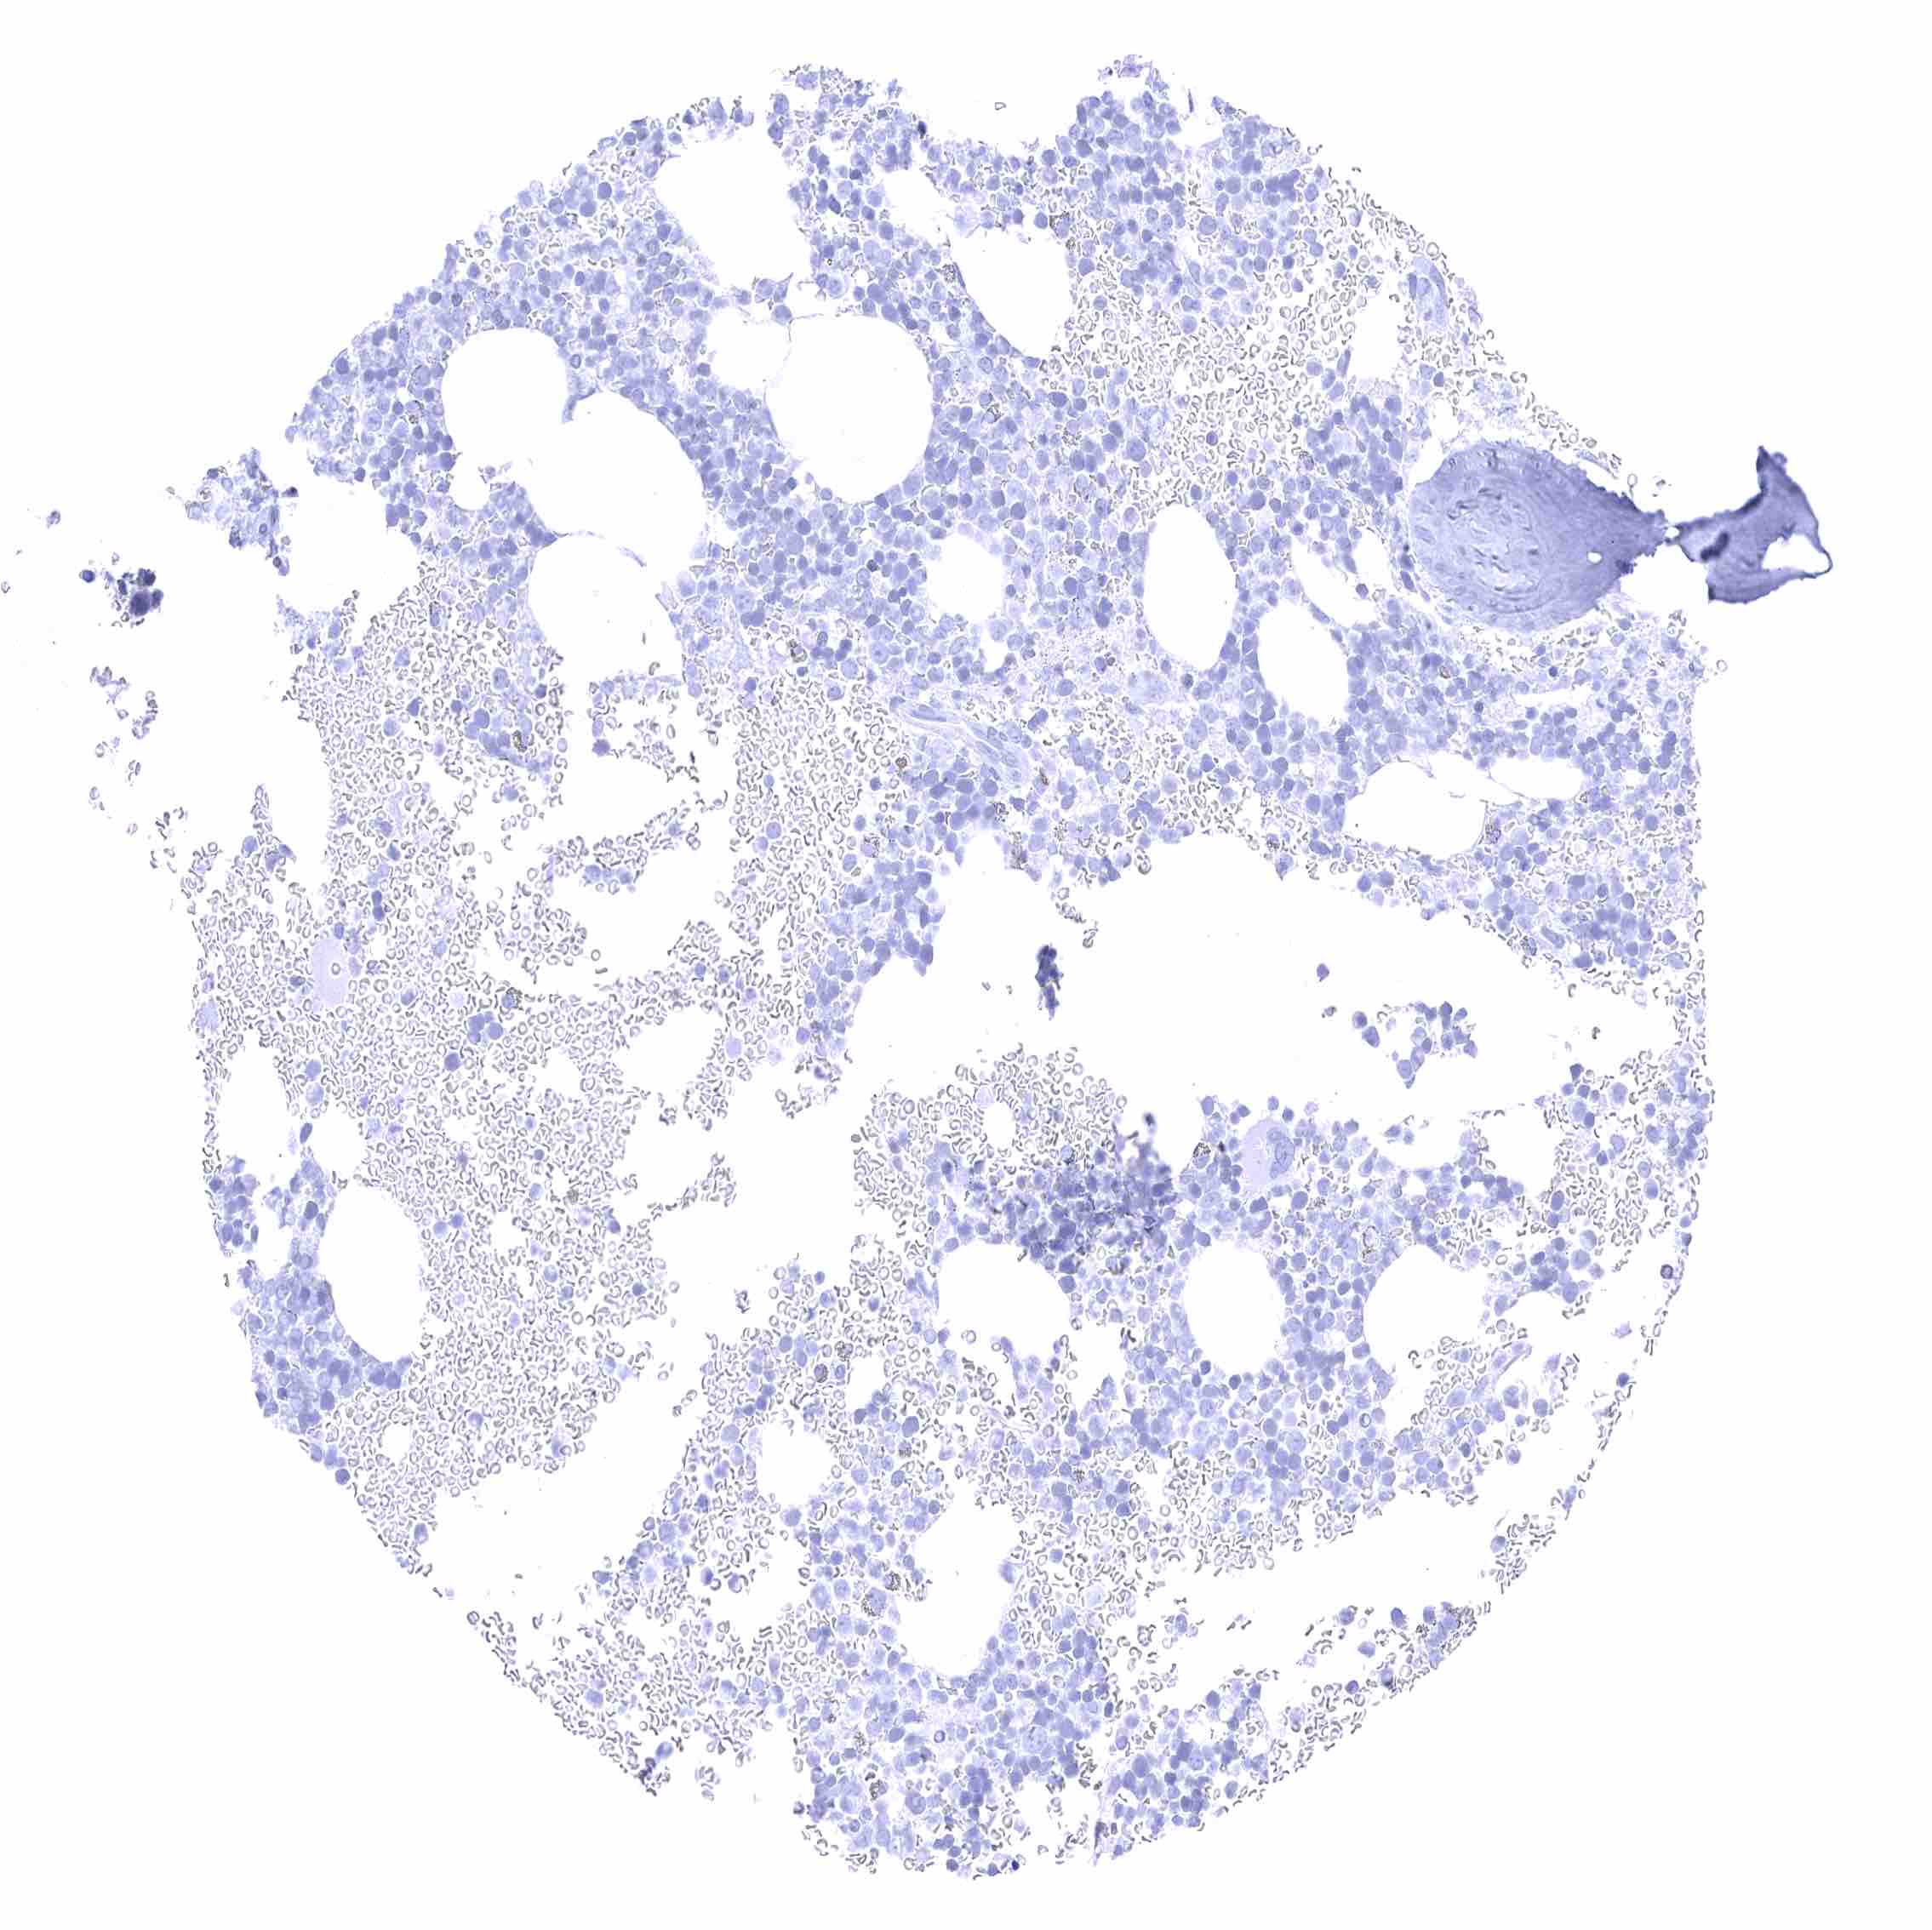

Tonsil – Membranous CD70 staining of variable intensity in subsets of cells (mostly lymphocytes). Most CD70 positive cells are interfollicular.